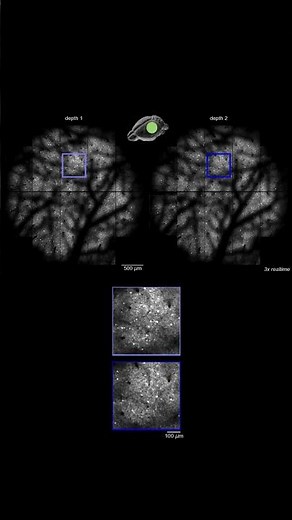

In vivo imaging of GCaMP6f-expressing neurons in the visual c

…

2-D images of nerve cells in the brain of a live mouse

已浏览 1.5万 次